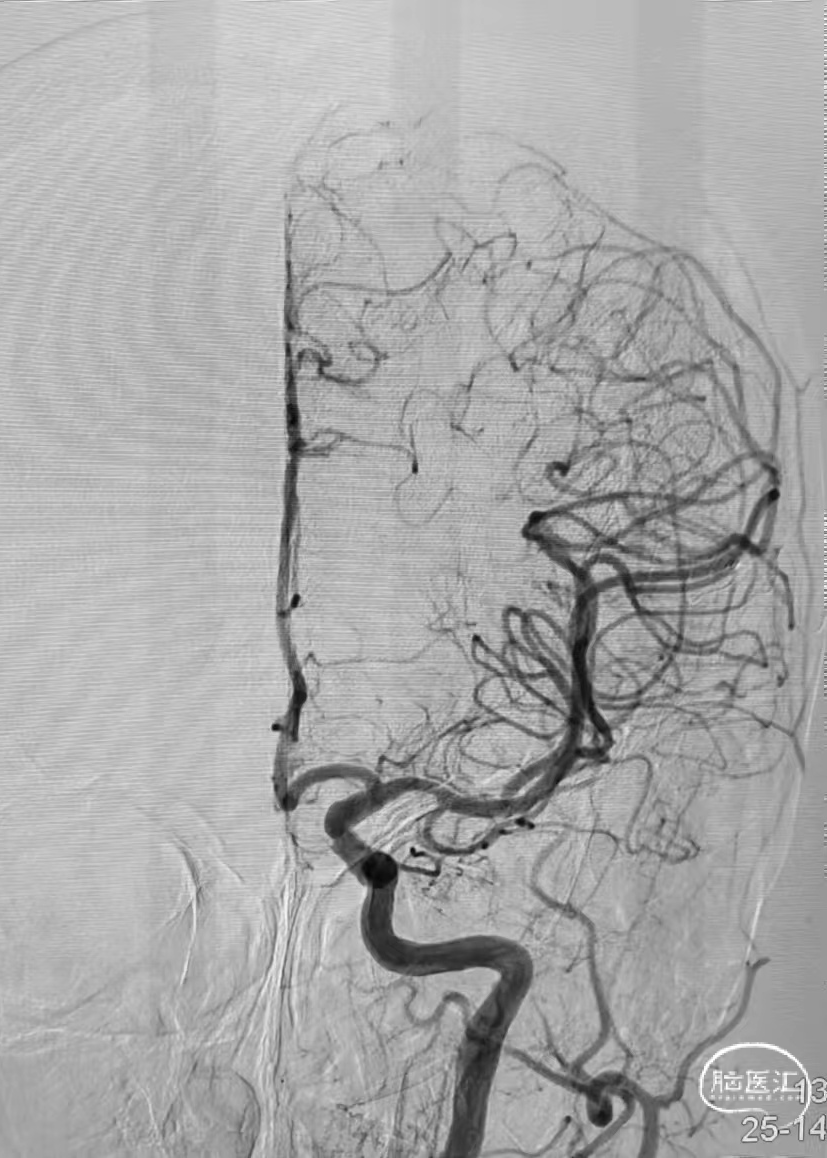

➤DSA

6F 长鞘导引至左侧颈内静脉末端。

测压导丝对横窦至乙状窦进行测压,静脉压差<2mmHg,未对狭窄段进行球囊扩张。

6F 长鞘导引至左侧乙状窦。

交换Command 18导丝超选至左侧横窦,将Echelon-10微导管置入静脉窦憩室。

路图下,沿Command 18导丝将8×40mm Xpert Pro支架输送至乙状窦,使用支架近远端marker点进行准确定位,整个推送过程顺利,无明显阻力。

Xpert Pro支架未展开状态下在憩室内尝试使用弹簧圈进行填塞,发现成篮困难。

随即释放Xpert Pro支架以覆盖憩室开口,支架打开后显影清晰,贴壁良好。使用微导管穿出支架网孔,并置入憩室内进行弹簧圈填塞。单微导管填塞过程弹簧圈成篮较为困难。

使用双导管继续在Xpert Pro支架辅助下进行弹簧圈填塞,再次造影显示:憩室内血液已完全阻滞,未见显影。

Xpert Pro支架在乙状窦内形态良好。静脉窦憩室闭塞完全。